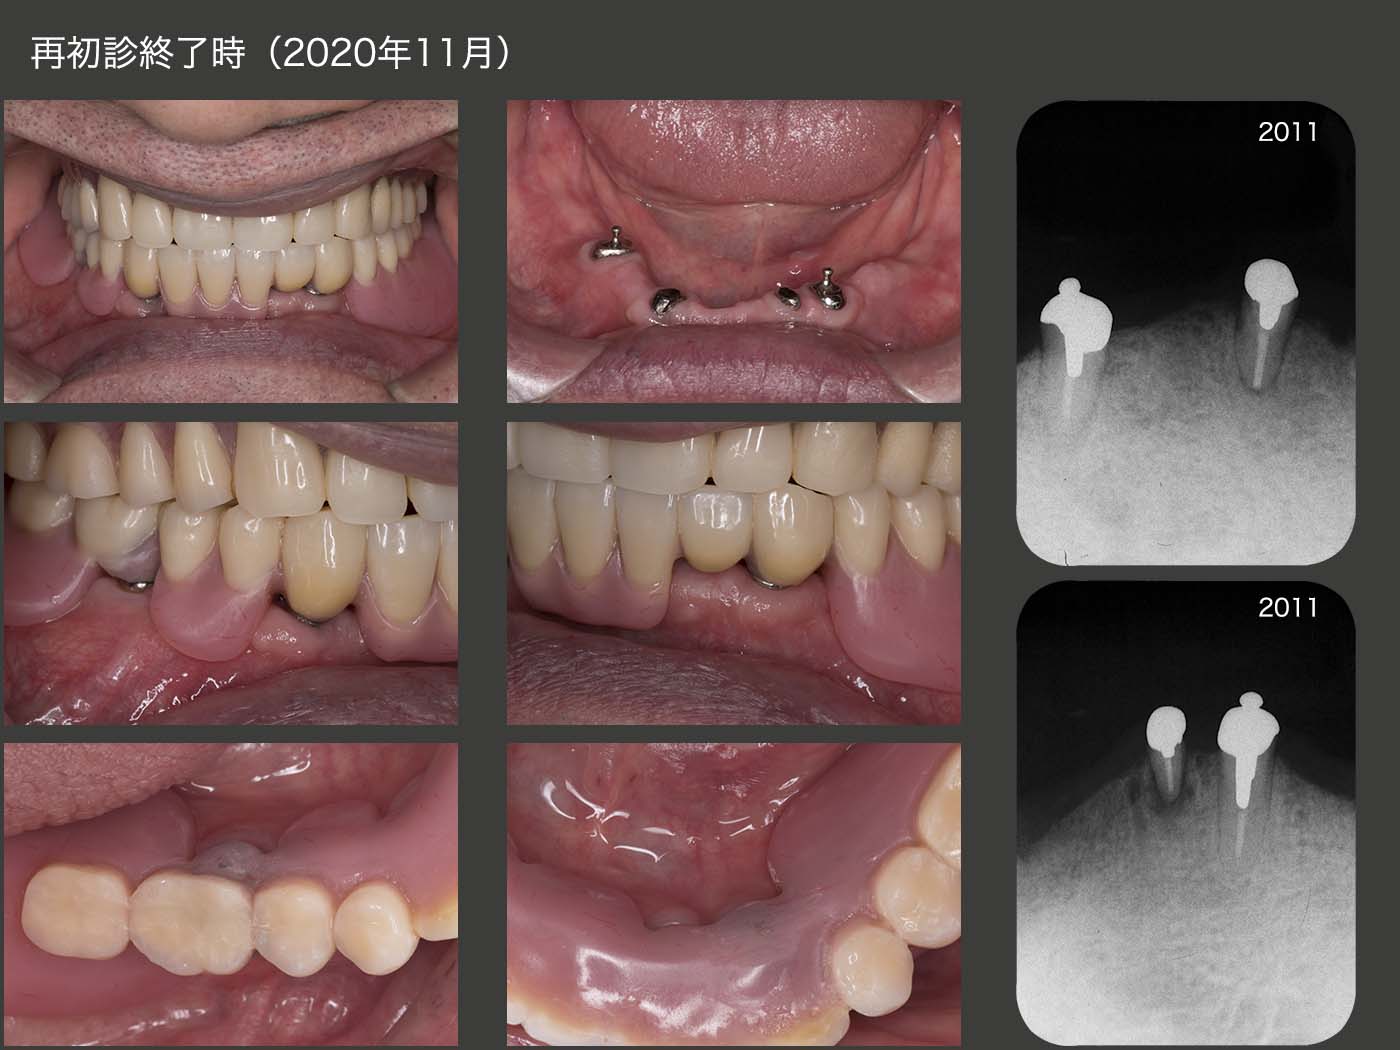

20年2月のリコール時,残念ながらう蝕が進行し,これ以上の放置は危険であることから再治療を行うことになった.今回は,積極的に支台歯辺縁歯肉の開放を行いたい旨を説明し,同意して頂いた.まず,旧義歯を改変し,特に舌側の開放部に異物感が生じるか否かの反応を確認した.つぎに6月,左右側に分けて歯冠長延長術を行い,歯肉縁上歯質の確保を行った.9月,OPAアタッチメントおよび根面板を再製作した.旧義歯を用いての咬合圧印象を行うことで咬合採得も同時に行った.デンチャースペースが十分とれるため,上部構造体は義歯床に埋め込む形態とした.